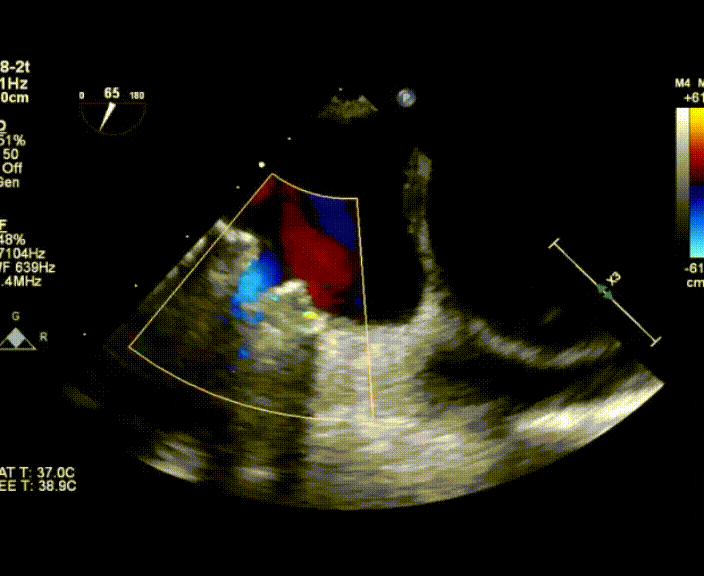

術(shù)中首先在局麻下穿刺股動(dòng)脈、股靜脈,完成心導(dǎo)管檢查評(píng)估后轉(zhuǎn)為全麻,在食道超聲引導(dǎo)下穿刺房間隔,穿刺成功后將加硬導(dǎo)絲送入左上肺靜脈建立軌道,根據(jù)患者病情行球囊預(yù)擴(kuò)張后植入6mm孔徑房間隔造孔支架,經(jīng)透視及食道超聲評(píng)估支架左右盤展開良好,夾持于房間隔兩側(cè),固定穩(wěn)定、位置良好,食道彩超顯示房水平右向左為主分流,分流孔直徑符合預(yù)期大小,心導(dǎo)管檢查評(píng)估達(dá)到預(yù)期效果,釋放造孔支架。術(shù)后12h患者下床活動(dòng),恢復(fù)順利,擬于近日完善術(shù)后評(píng)估后出院。